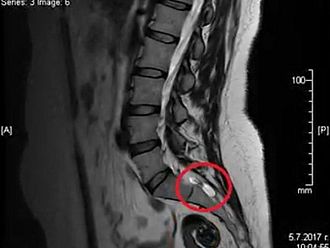

Оттам допълват, че е необходимо строго прецизиране на текстовете, свързани с диагностиката и физиотерапията на периневралните кости на Тарлов, тъй като има диагностични и физиотерапевтични процедури, които са противопоказани за тях.